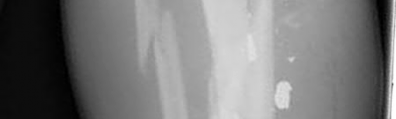

Figures A and B show radiographs of a comminuted AO/OTA C3 fracture of the distal tibia. The most appropriate steps in the management of this patients injury would include: Closed reduction and splinting, external fixation, CT scan, and delayed open reduction internal fixation in this sequence.

Infection and wound healing problems are common with comminuted distal tibia fractures due to an increased incidence of soft-tissue complications associated with the operative management. Patients with a history of diabetes and smoking are at further risk. To decrease the risk of complications in this patient, a two-staged, delayed open reduction internal fixation technique is the best option for the treatment of severe pilon fractures.

Patterson et al. reviewed 23 consecutive patients with comminuted distal tibia fractures. They showed 0% infections or wound-healing problems in their patient population treated with a two-staged protocol. Their protocol involved fibula fixation with an intramedullary implant and application of a medial external fixator to to regain length and restore anatomic alignment. Re-evaluation of the limb occurred ten to fourteen days later for definitive fixation.

Sirkin et al. retrospectively reviewed 40 closed and 82 open pilon fractures (AO types 43A-C) that were treated with staged surgical management (avg. time from ext. fix. to formal reconstruction was 14 days (range 4 to 31) They reported 17% post-operative wound complication in the closed group and 11% post-operative wound complication in the open group (Gustilo Type I-III). They suggest the technique was successful in both closed and open pilon fractures.